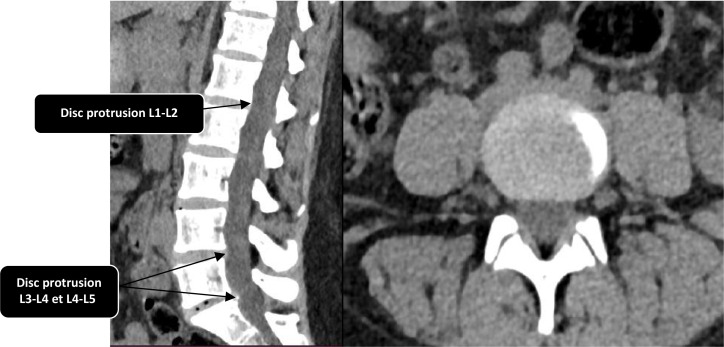

Psoas abscess is a rare infection historically associated with tuberculosis (TB), although non-tuberculous bacterial causes, particularly Staphylococcus aureus, have become increasingly common. This type of abscess can be either primary or secondary, and its diagnosis remains challenging due to the non-specific nature of clinical signs. Imaging and microbiological analyses are essential for establishing the diagnosis. We report the case of a 22-year-old patient with no significant medical history, who presented with persistent mechanical low back pain for 18 months. Initial computed tomography revealed a non-compressive disc protrusion, leading to treatment with non-steroidal anti-inflammatory drugs, without improvement. Further investigations revealed an extrapulmonary spinal localization of TB in an immunocompetent patient, with bilateral psoas abscesses caused by Mycobacterium tuberculosis, confirmed by the Ziehl-Neelsen staining, auramine staining, culture on Löwenstein-Jensen medium and GeneXpert PCR. Anti-TB treatment was initiated, resulting in favourable clinical evolution.